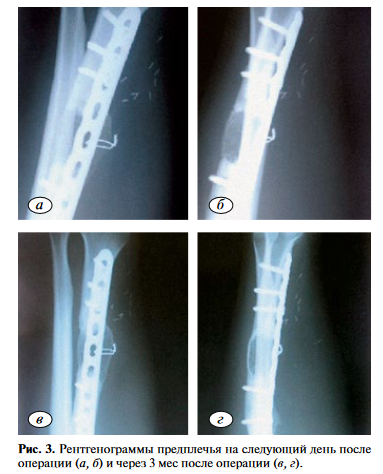

Клинический пример 2. Пациент А. в результате высокоэнергетической травмы получил открытый перелом правой лучевой кости со смещением отломков. Прооперирован в день получения травмы: выполнены остеосинтез лучевой кости аппаратом Илизарова и первичная хирургическая обработка раны. На контрольных рентгенограммах выявлены отсутствие признаков консолидации, формирование дефекта лучевой кости в связи с чем в октябре того же года прооперирован повторно: выполнены остеосинтез лучевой кости спицестержневым аппаратом, костная аутопластика из гребня подвздошной кости. При последующем наблюдении пациента в течение 2 лет обнаружены признаки формирования ложного сустава лучевой кости. Пациенту выполнена васкуляризированная костная аутопластика свободным трансплантатом из медиального мыщелка БК (рис. 3, а, б).

Результат, полученный через 3 мес после операции, представлен на рис. 3, в, г.